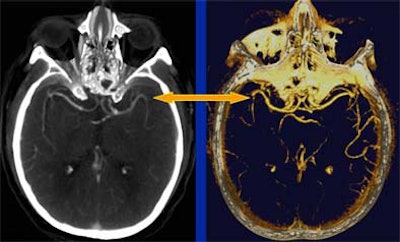

| Even in a patient presenting with acute right hemiparesis, routine noncontrast CT can be normal. Images courtesy of Dr. Jay Cinnamon. |